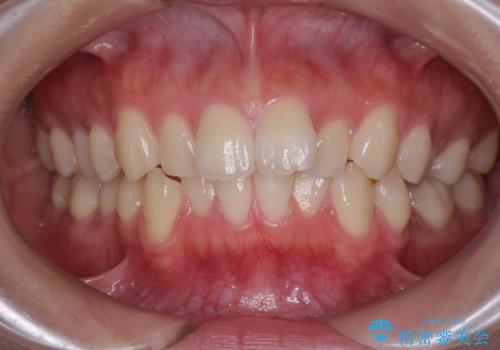

- デコボコを気にして来院された患者様です。

インビザラインでもワイヤー装置でも対応可能でしたが、自己管理の煩わしさの観点から、楽して治療のできるワイヤー装置を選択されました。

抜歯するほどではないものの、やや口元の突出感が気になっていたので、補助装置により上顎臼歯を後方に移動させることで、突出感改善を図ることとしました。